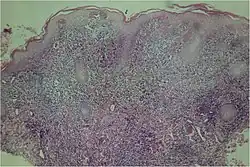

A microscopic examination of a biopsy of a yaw may show skin with clear epidermal hyperplasia (a type of skin thickening) and papillomatosis (a type of surface irregularity), often with focal spongiosis (an accumulation of fluid in a specific part of the epidermis). Immune system cells, neutrophils and plasma cells, accumulate in the skin, in densities that may cause microabscesses.

Warthin–Starry or Levaditi silver stains selectively stain T. pallidum, and direct and indirect immunofluorescence and immunoperoxidase tests can detect polyclonal antibodies to T. pallidum's. Histology often shows some spatial features that distinguish yaws from syphilis (syphilis is more likely to be found in the dermis, not the epidermis, and shows more endothelial cell proliferation and vascular obliteration).[2]